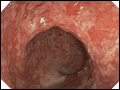

| Figure 295-5 Colonoscopy with acute ulcerative colitis: Severe colon inflammation with erythema, friability, and exudates. (Courtesy of Dr. M. Hamilton, Gastroenterology Division, Department of Medicine, Brigham and Women's Hospital, Boston, Massachusetts; with permission.) | |

view large |